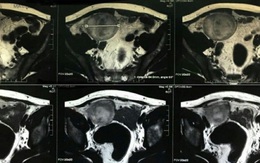

Một bệnh nhân lưỡng giới mắc ung thư tinh hoàn ẩn hiếm gặp

Mặc dù có buồng trứng nhưng một bệnh nhân tại Đồng Nai vừa được các bác sĩ phát hiện mắc ung thư tinh hoàn ẩn.

Làm bố của 3 đứa con, mới biết tinh hoàn còn lại ẩn mình trong ổ bụng

TTO - Nam bệnh nhân 44 tuổi ở Phú Thọ, đã có vợ và 3 con, từ nhỏ đã không thấy tinh hoàn phải trong bìu, gần đây bệnh nhân thấy đau ở hố chậu phải, kích thước 7cm. Đó chính là tinh hoàn của bệnh nhân nay đã hình thành khối u.